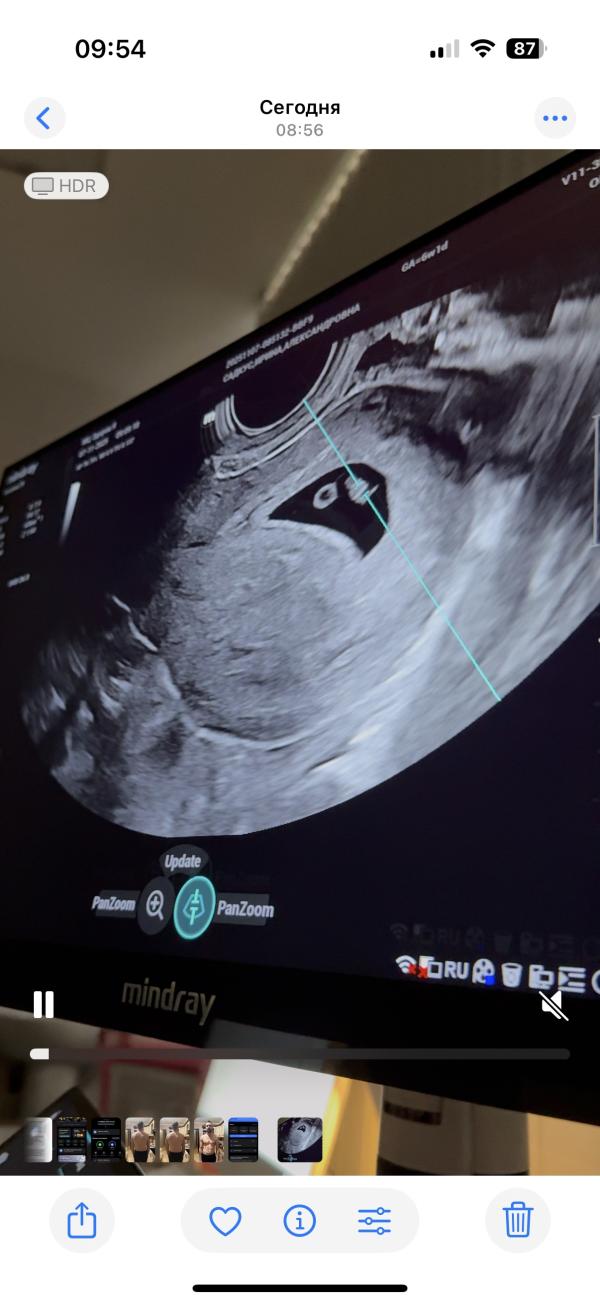

Сердцебиение на 6 неделе беременности: первое УЗИ

По узи на 2 дня побольше)6 недель и 4 дня.

У нашей креветки уже сердцебиение ❤️